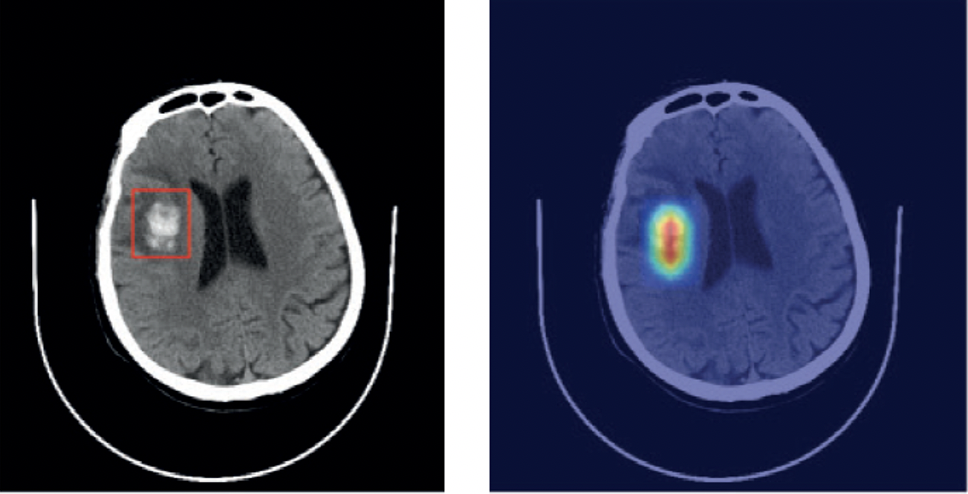

Self-taught AI detects disorders from head scans

This intuitive AI can sort through scans to diagnose stroke, brain haemorrhage, brain tumors and skull fractures.